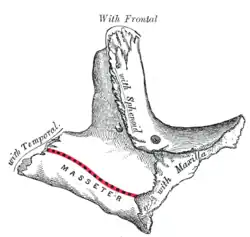

Osso zigomático esquerdo. Superfície de Malar.

Osso zigomático esquerdo. Superfície de Malar. Osso zigomático esquerdo. Superfície temporal.

Osso zigomático esquerdo. Superfície temporal. Visão lateral do crânio.